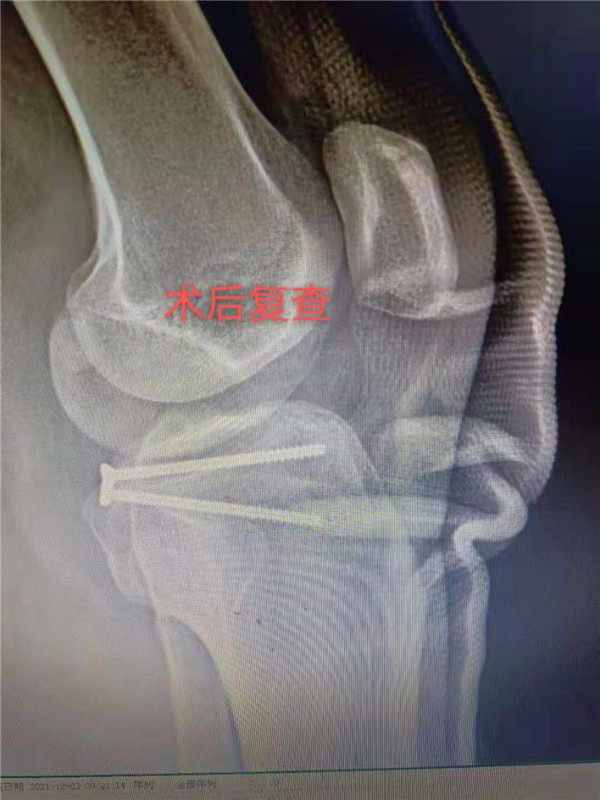

12月2日,景德镇市第三人民医院骨一科团队成功为一位后叉韧带止点撕脱性骨折患者施行了改良小切口下后叉韧带止点撕脱性骨折复位内固定止点重建术手术,帮助患者免受传统手术创口较大之苦。改良小切口和传统手术方式相比损伤小,术中无任何肌性、腱性组织的损伤。该手术是一种微创手术,它具有创伤小,术后并发症少,减轻疼痛,并在一定程度上改善功能等优势,减轻炎症和疼痛,从而使患者的损伤达到最小、康复更快。

患者李某,今年37岁,因几日前跨越障碍物时不慎摔倒,左膝着地,当即觉得左膝疼痛难忍、活动受限。于12月1日入市三院就诊,入院后查左膝正侧位片、左膝CT三维重建等检查:提示后交叉韧带止点撕脱性骨折。经骨一科主任邵建敏和副主任医师徐军志反复查阅相关资料及科室病例讨论后,充分与患者及家属沟通并征得同意后,建议行改良小切口下行止点重建术。徐军志副主任医师于12月2 日在腰硬联合麻醉下为患者行左膝后叉止点撕脱性骨折复位内固定止点重建术,术后切口长约3CM。术后患者无不适感,症状明显改善,疼痛明显缓解,并于术后2天出院。

“仅有1个不到3厘米的切口,而且损伤小,术后关节功能恢复快,花费也比传统手术少。”术后患者及家属无比开心,不断向医护人员道谢。